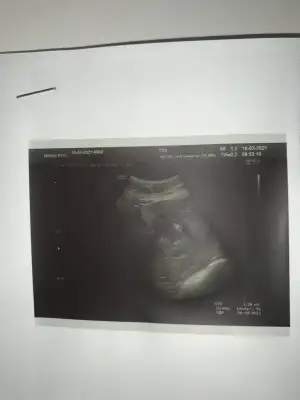

8 hafta çok erken ama bana da bakabilir misiniz 🥰

Merhaba. Rica etsem benim usmya tahmin yapar mısınız?

12+2 günlüktü burda. Karından detaylı ultrasondu.

Doktor benzetme yaptı ama kesin değil dedi.doktorla aynı olursa oyumu veririm❤️